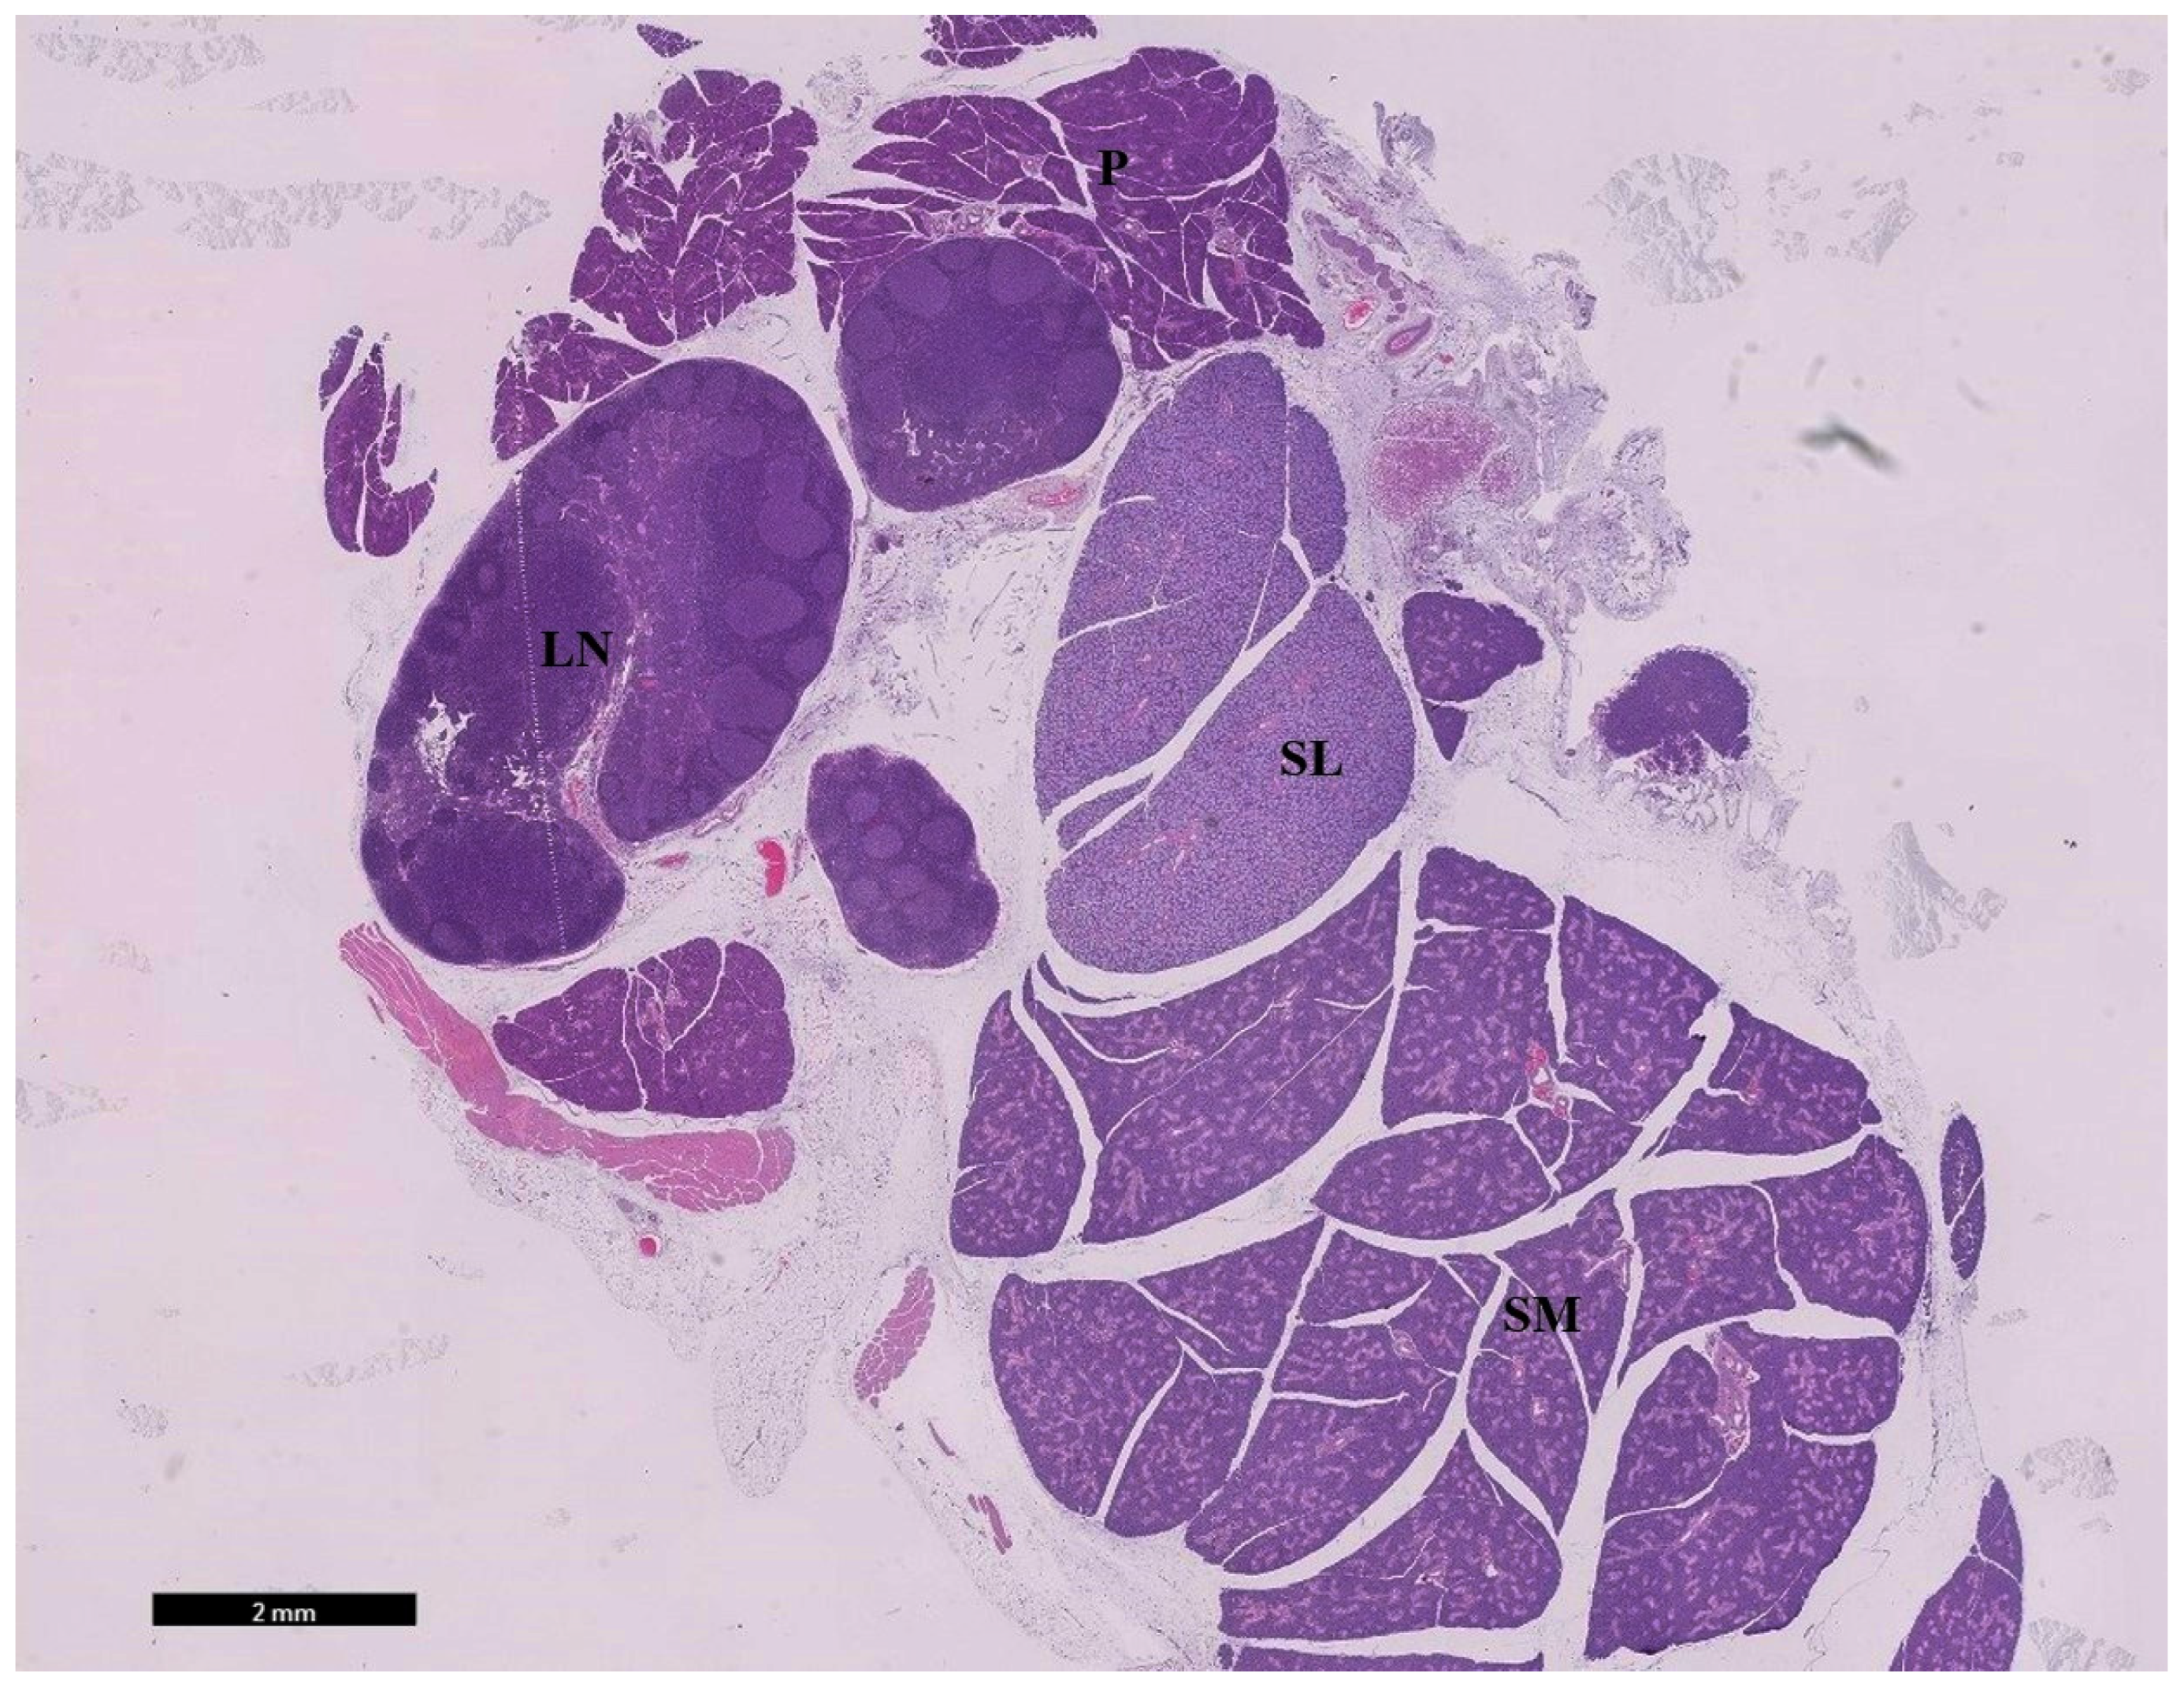

3.1.1. Examination of Hematoxylin and Eosin-Stained Sections

- Amano, O.; Mizobe, K.; Bando, Y.; Sakiyama, K. Anatomy and histology of rodent and human major salivary glands—Overview of the Japan salivary gland society-sponsored workshop. Acta Histochem Cytochem. 2012, 45, 241–250. [Google Scholar] [CrossRef]